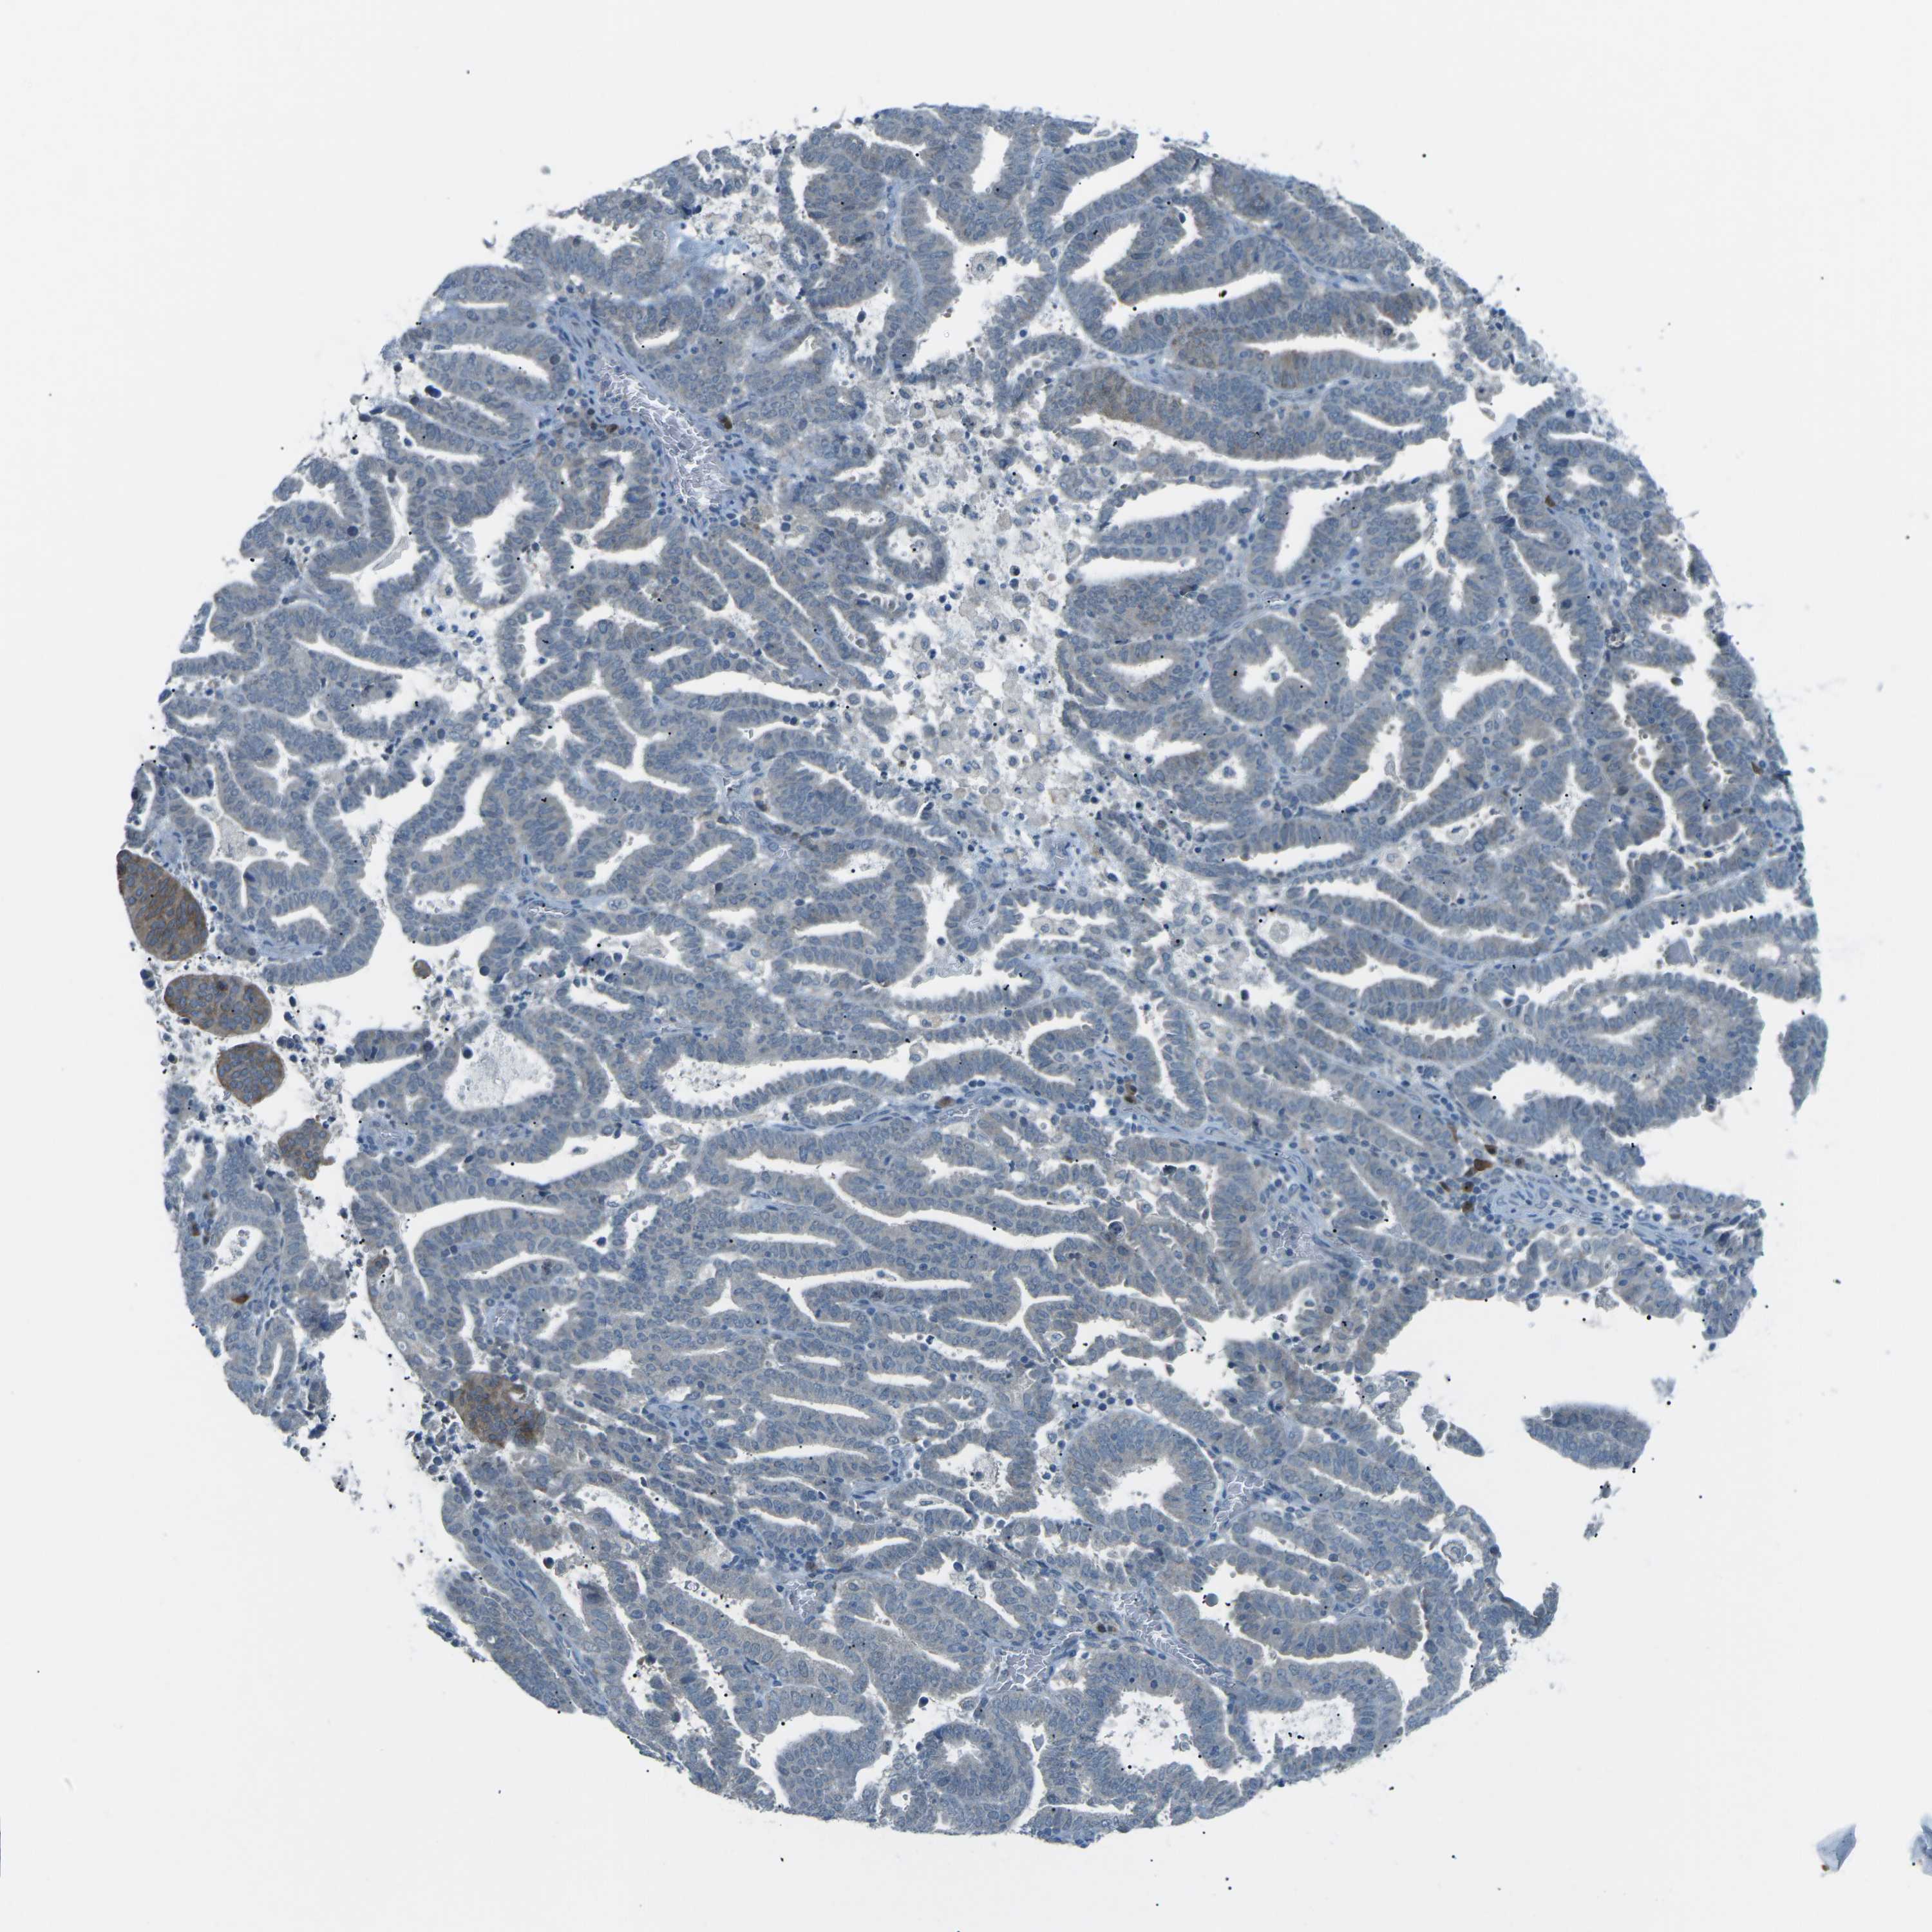

ENDOMETRIAL CANCER - Protein expressioni

A mouse-over function shows sample information and annotation data. Click on an image to view it in a full screen mode. Samples can be filtered based on level of antibody staining by selecting one or several of the following categories: high, medium, low and not detected. The assay and annotation is described here.

Note that samples used for immunohistochemistry by the Human Protein Atlas do not correspond to samples in the TCGA dataset.

Antibody stainingi

Antibody staining in the annotated cell types in the current human tissue is reported as not detected, low, medium, or high, based on conventional immunohistochemistry profiling in selected tissues. This score is based on the combination of the staining intensity and fraction of stained cells.

Each image is clickable and will lead to virtual microscopy that enables deeper exploration of all samples and also displays staining intensity scores, fraction scores and subcellular localization as well as patient and tissue information for each sample.

Antibody HPA006563

Antibody HPA006564

Antibody CAB003844

Antibody CAB016290

Staining

High

Medium

Low

Not detected

Intensity

Strong

Moderate

Weak

Negative

Quantity

>75%

75%-25%

<25%

None

Location

Nuclear

Cytoplasmic/membranous

Cytoplasmic/membranous,nuclear